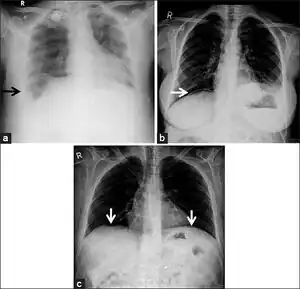

Pseudopneumoperitoneum a) Chest radiograph of Chilaiditi syndrome showing large bowel loops arrow under the diaphragm b) linear atelectasis c) loculated air beneath the diaphragms following colonoscopy[5]

As differential diagnoses, a subphrenic abscess, bowel interposed between diaphragm and liver (Chilaiditi syndrome), and linear atelectasis at the base of the lungs can simulate free air under the diaphragm on a chest X-ray.